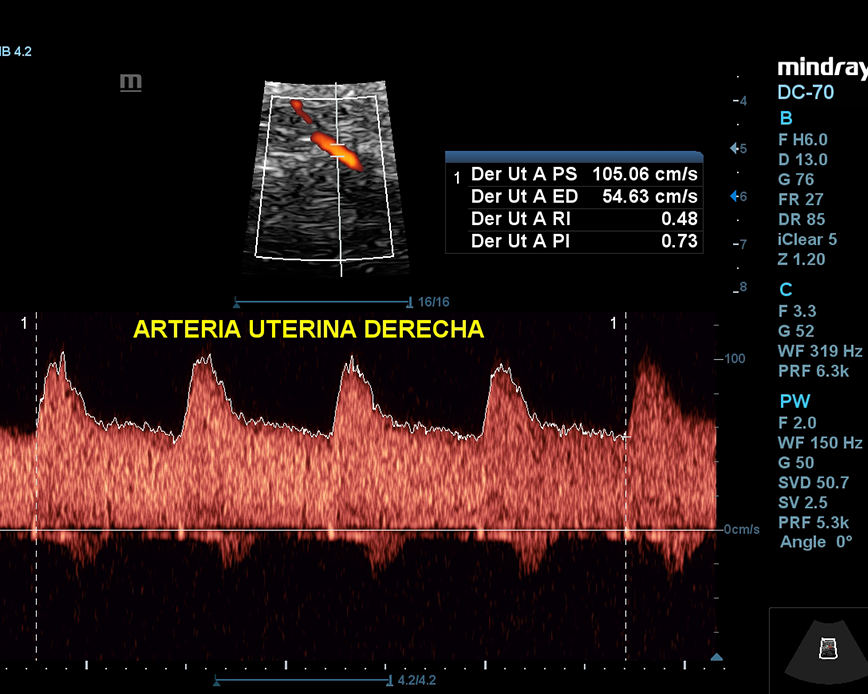

Esta ecografía sirve para evaluar la hemodinamia materno-fetal y detectar problemas de crecimiento como el RCIU (Restricción del Crecimiento Intrauterino) y el riesgo de preeclampsia (presión arterial alta durante el embarazo). Además, nos permite evaluar el cordón umbilical y detectar circulares de cordón simple, doble o triple.